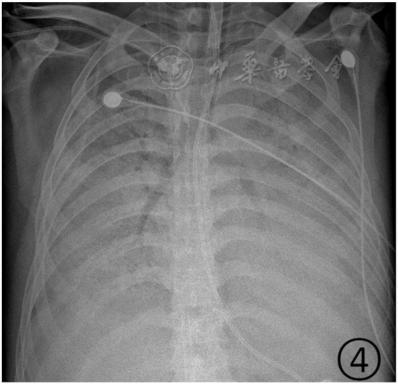

若病毒大量復制,或者患者免疫功能較弱時,會發展為危重癥。此時病毒會攻擊多個肺葉,肺泡損傷彌漫,病變范圍擴大、融合,造成雙肺實變,即從CT上看,患者的肺部呈一大片的白色狀,醫學上稱之為“白肺”。這種情況會嚴重影響肺換氣,患者需要持續吸氧。

▲白肺(圖片來自網絡)

按照國家衛健委發布的新型冠狀病毒肺炎試行第六版診療方案之中的臨床分型,新冠肺炎分為輕型、普通型、重型及危重型。在患者的肺部CT中,輕型者沒有比較明顯的肺炎改變;普通型者以肺部出現局限性斑片狀或很多節段性片狀“病灶”為主(圖②);重型者雙肺可出現較多的白色小斑片“病灶”,部分融合成大片狀“病灶”(圖③);危重型者會有“白肺”表現(圖④)。

▲從上到下依次為普通型、重型及危重型新冠肺炎患者的肺部CT表現(圖片來自網絡)